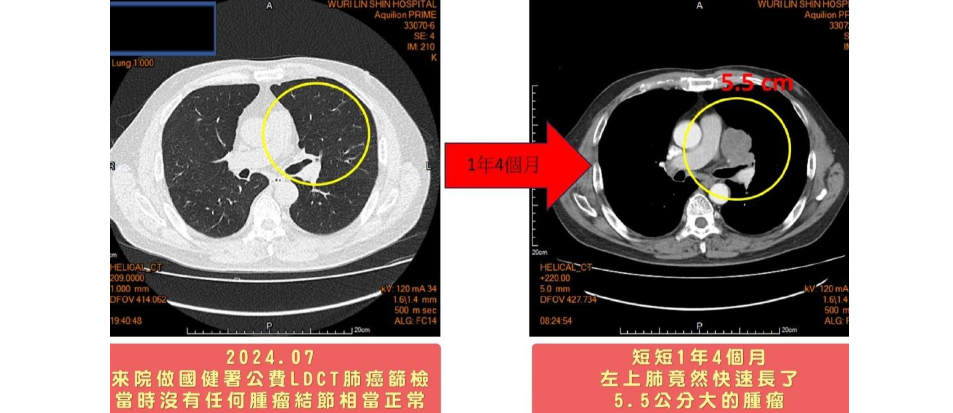

台中一名63歲黃姓男子每天都要抽兩包菸,菸齡長達40年之久,日前他接受國健署提供的公費低劑量電腦斷層掃描肺癌篩檢,檢查結果正常,但短短1年4個月後,竟發現左上肺長出5.5公分大的腫瘤,烏日林新醫院癌症副院長暨胸腔內科許人文醫師診斷為「小細胞肺癌」末期,不治療的話存活期僅剩3個月,但在化療、胸部放射線照射治療後成功擊退「癌王」,黃男趕緊戒菸,遠離肺癌威脅。